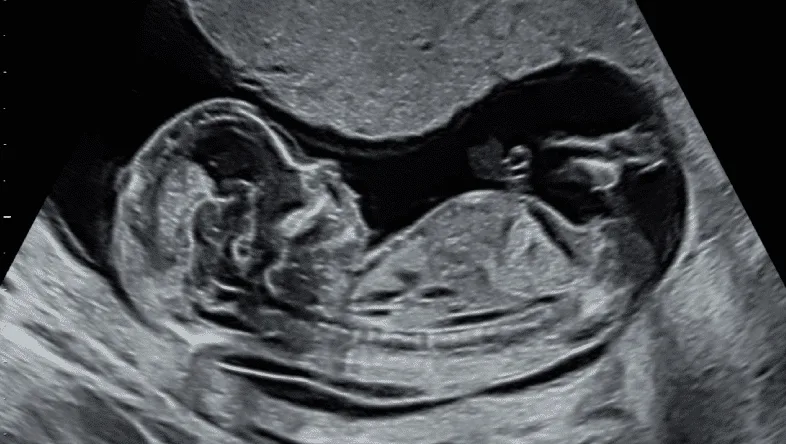

- Are expecting twins or multiples

During the scan, these parameters are checked:

- Biometric Measurements: Head Circumference, Abdominal Circumference, Femur Length